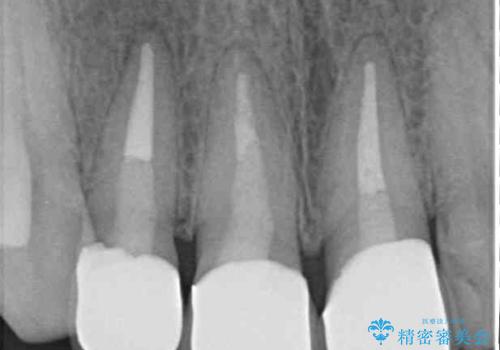

- 上の前歯のセラミッククラウンが古くなったことと、下の前歯のデコボコを気にして来院された患者様です。

前歯は一部根管治療を行った後にオールセラミッククラウンに補綴することとしました。